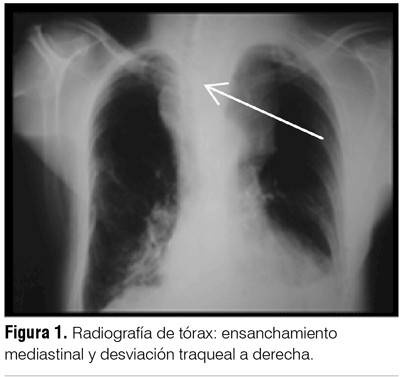

La radiografía de tórax mostró ensanchamiento mediastinal y desviación traqueal a derecha (figura 1). La tomografía cérvico-mediastinal evidenció tumoración cervical de 8 cm que comprimía y desplazaba tráquea, con luz traqueal de 1 cm y conglomerados ganglionares de cuello (figura 2 A). Proceso de consolidación en hemitórax izquierdo con derrame pleural (DP) (figura 2 B).